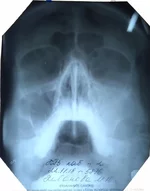

Вот решила к другому сходить врачу(в той же поликлиннике), он сделал снимок,увидел в носу какие то искривления, бугорок, говорит ей гайморит , надо пробивать чистить и т.д.. Вот тут Я совсем не понял, как врачи наши лечат(один одно,другой другое), решил проконсультироваться немного. Что нам делать и как поступить?

снимок прикрепил, скажите по нем видно чтото?

Забыл, есть старое еще фото 2010года( прикрепил)